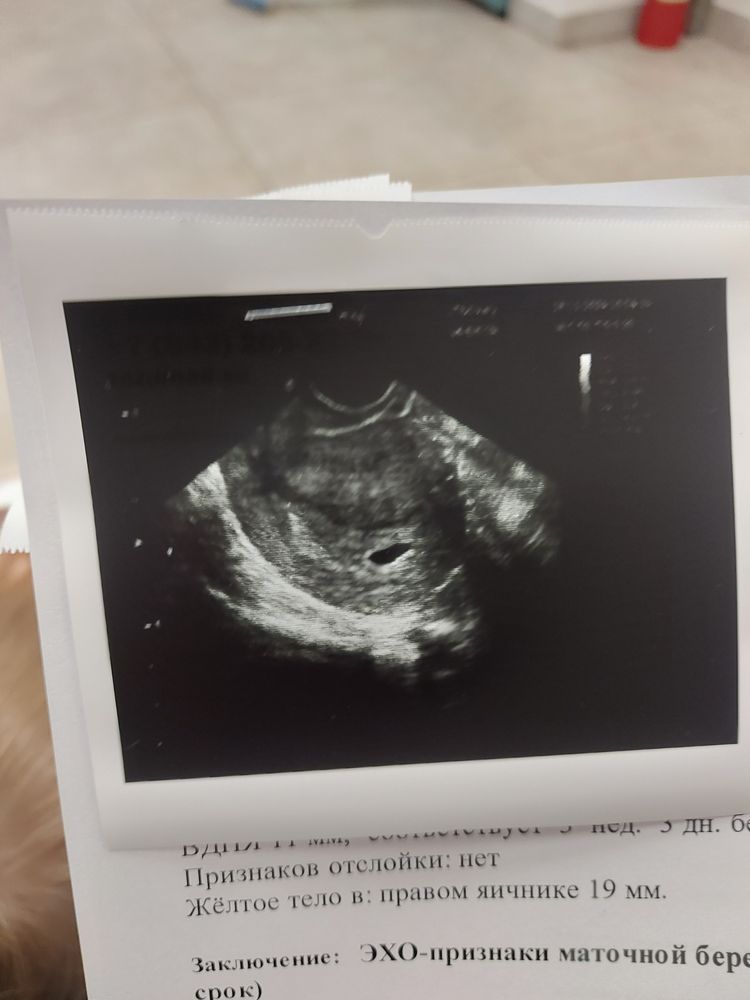

Срок 3,3нед, размер 11мм. Мне кажется крупновато как то...

Срок по месячным 5,2нед.